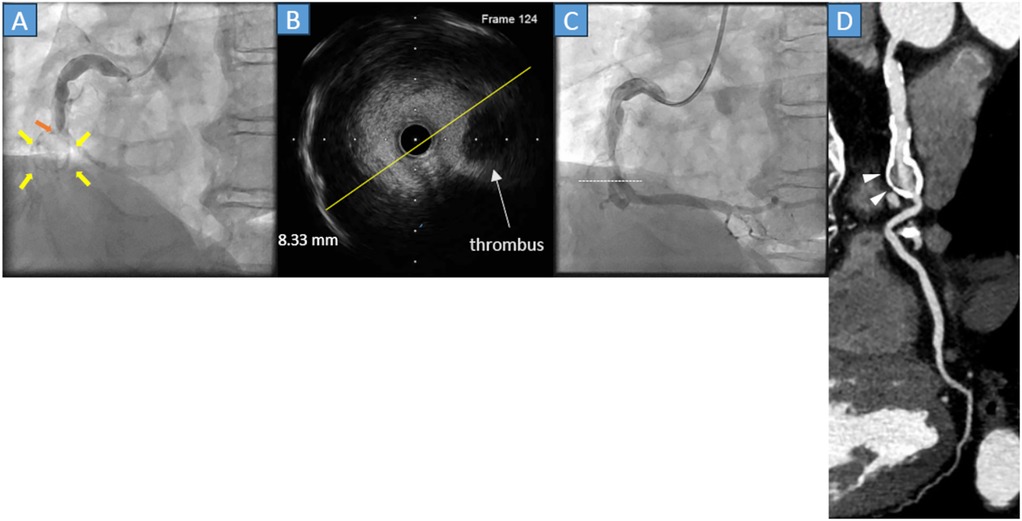

A 60-year-old man with hypercholesterolemia visited our emergency department because his symptoms had worsened 6 h before hospital admission. His history of Kawasaki disease was unclear. Electrocardiography (ECG) showed ST-segment elevation in leads II, III, and aVF, and his cardiac troponin T level was 0.030 ng/mL (normal range, <0.014 ng/mL). As an acute inferior ST-elevation myocardial infarction (STEMI) was suspected, urgent coronary angiography (CAG) was performed, and revealed total occlusion of the middle segment of the right coronary artery (RCA) (Figure 1A, orange arrow), along with severe calcification of the aneurysm (Figure 1A, yellow arrows). In March 2024, subsequently, percutaneous coronary intervention (PCI) was performed. A 0.014-inch guidewire was introduced, then intravascular ultrasound (IVUS) was employed. IVUS revealed an exceeding 8 mm coronary aneurysm (Figure 1B yellow line, Figure 1C white dots), thrombus, severe calcification, and substantial differences in diameter between the distal and proximal lesions. Stent placement was avoided, owing to IVUS findings. A 3.0*20 mm paclitaxel DCB angioplasty was performed following predilatation with a 3.0*13 mm scoring balloon. The final CAG revealed thrombolysis in myocardial infarction grade III flow in the RCA (Figure 1C) without dissection. After PCI, the patient was prescribed aspirin, clopidogrel, and statins for five months. After five months, clopidogrel was discontinued. Aspirin, warfarin, and statins were administered. During follow-up, he reported no chest symptoms.

Four medical images showing coronary artery diagnostics: \n\nA) Angiogram with red and yellow arrows pointing to areas of interest in the artery. \n\nB) Intravascular ultrasound image with a highlighted thrombus and a measurement of eight point three three millimeters. \n\nC) Angiogram with a dashed line on a coronary section. \n\nD) CT scan showing a narrowed section of the artery marked by white arrowheads.

Figure 1. (A) Coronary angiography (CAG) reveals acute total occlusion of the middle right coronary artery (orange arrow) with a circular calcified structure (yellow arrows). (B) The cross-sectional image of the intravascular ultrasound (IVUS) reveals that the diameter of the lesion was 8.33 mm (yellow line) with thrombus and calcification of the vessel wall. (C) The final CAG reveals a Thrombolysis in Myocardial Infarction grade III flow. The white dots in the angiography correspond to the cross-sectional IVUS image. (D) Cardiac computed tomography in the chronic phase reveals that preserved right coronary flow and the presence of a saccular aneurysm with severe calcification (gray arrowheads).

Approximately 1 year and 1 month after PCI (April 2025), cardiac coronary computed tomography (CT) was performed and showed the lesion remained patent with a saccular right coronary artery aneurysm with heavy calcification but no enlargement compared with the lesion size in the acute phase (Figure 1D, white arrowheads).